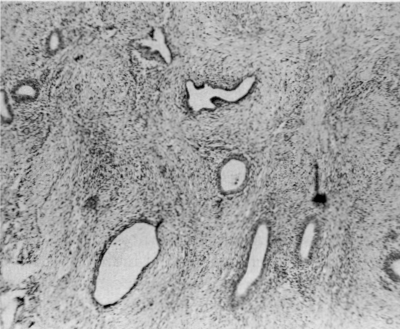

Une loupe a été utilisée pour examiner le péritoine du cul-de-sac de Douglas dans tous les cas. Dans un cas, une minuscule plaque blanchâtre, d’environ 200 µm de diamètre, a été identifiée. Elle a été excisée, fixée dans du formol et colorée à l’hématoxyline et à l’éosine pour la microscopie optique.

Les observations microscopiques concernant la plaque provenant du cul-de-sac de Douglas d’un nourrisson de 2 mois ont montré une structure glandulaire aplatie avec un épithélium bien défini entouré d’un stroma douteux (figure 5).